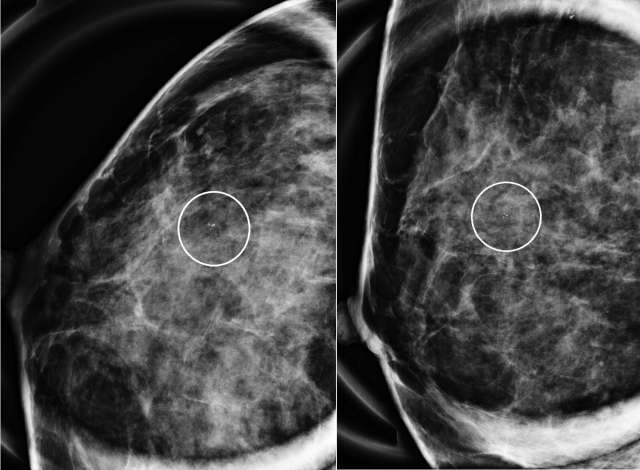

Case: Atypical Ductal Hyperplasia Figure 2

Case 2: Magnification CC (left) and ML (right) views from a diagnostic mammogram demonstrate coarse heterogeneous calcifications measuring 6 mm with grouped distribution in the upper outer quadrant of the right breast at middle depth located 3 centimeters from the nipple. Pathology demonstrated atypical ductal hyperplasia.